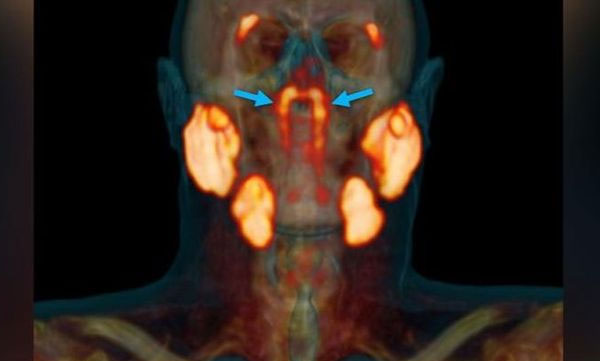

പി.എസ്.എം.എ പി.എ.ഇ സി.ടി പരിശോധനയിലാണ് 1.5 ഇഞ്ചോളം വലുപ്പമുള്ള പുതിയ സെറ്റ് ഗ്രന്ഥികള് കണ്ടെത്തിയത്.

പുതുതായി കണ്ടെത്തിയ ഉമിനീര് ഗന്ധികളുടെ സ്ഥാനം മൂക്കിനു പിന്വശത്തായാണ്. മൂക്കിനും വായയ്ക്കും പിന്നിലായുള്ള തൊണ്ടയുടെ ഭാഗം നനയ്ക്കാനുള്ള ഉമിനീര് ഉത്പാദിപ്പിക്കുകയാണ് ഇവയുടെ ഉപയോഗമെന്നാണ് ശാസ്ത്രജ്ഞര് പറയുന്നത്. റേഡിയോതെറാപ്പി ആന്റ് ഓങ്കോളജി ജേണലിലാണ് പുതിയ പഠനം പ്രസിദ്ധീകരിച്ചത്.

ട്യൂബേറിയല് ഉമിനീര് ഗ്രന്ഥികള് എന്നാണ് പുതുതായി കണ്ടെത്തിയ ഗ്രന്ഥികള്ക്ക് പേരിട്ടിരിക്കുന്നത്. ടോറസ് ടൂബേറിയസ് എന്ന ഭാഗത്ത് സ്ഥിതി ചെയ്യുന്നതുകൊണ്ടാണ് ഇവയ്ക്ക് ഈ പേര്.